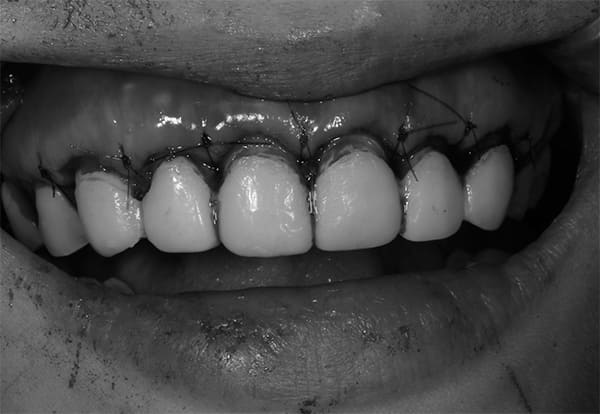

手術時

こちらがOPE時の写真です。

最終補綴物の形態に調和するよう歯肉ラインを整え、生物学的幅径(biologic width)を確保するために、必要な範囲で歯槽骨の整形(骨整形)を行いました。